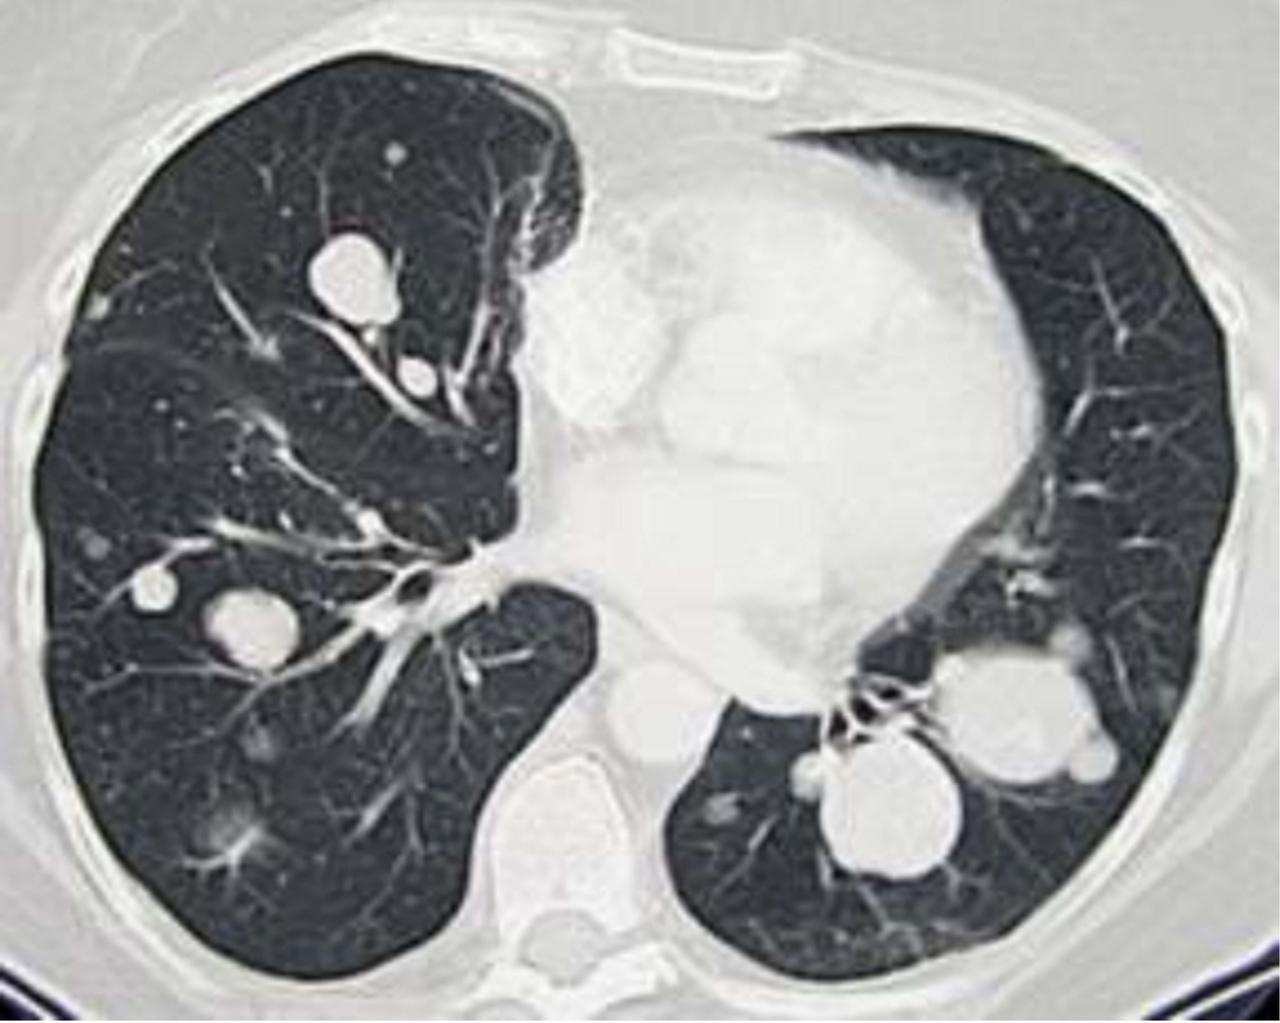

Quel est votre diagnostic ?

Il s'agit de l'aspect tomodensitométrique de métastases pulmonaires multiples en lâcher de ballons. Il s'agit ici de métastases multiples d'un sarcome des parties molles, traité par chimiothérapie. Si plus de 80 % des lésions cancéreuses ont des bords spiculés, près de 30 % des lésions infectieuses ont des limites floues. De même, des contours nets et bien délimités caractérisent généralement les lésions bénignes (80 % des cas), mais sont observés aussi en cas de lésion sarcomateuse, primitive ou métastatique comme ici.